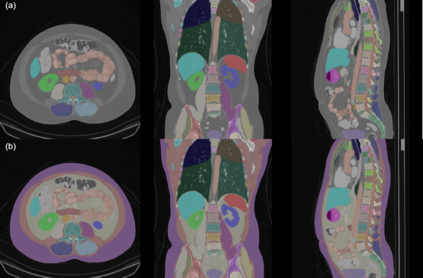

Purpose: The distribution of visceral adipose tissue (VAT) in cystectomy patients is indicative of the incidence of post-operative complications. Existing VAT segmentation methods for computed tomography (CT) employing intensity thresholding have limitations relating to inter-observer variability. Moreover, the difficulty in creating ground-truth masks limits the development of deep learning (DL) models for this task. This paper introduces a novel method for VAT prediction in pre-cystectomy CT, which is fully automated and does not require ground-truth VAT masks for training, overcoming aforementioned limitations. Methods: We introduce the Kernel density Enhanced VAT Segmentator ( KEVS), combining a DL semantic segmentation model, for multi-body feature prediction, with Gaussian kernel density estimation analysis of predicted subcutaneous adipose tissue to achieve accurate scan-specific predictions of VAT in the abdominal cavity. Uniquely for a DL pipeline, KEVS does not require ground-truth VAT masks. Results: We verify the ability of KEVS to accurately segment abdominal organs in unseen CT data and compare KEVS VAT segmentation predictions to existing state-of-the-art (SOTA) approaches in a dataset of 20 pre-cystectomy CT scans, collected from University College London Hospital (UCLH-Cyst), with expert ground-truth annotations. KEVS presents a 4.80% and 6.02% improvement in Dice Coefficient over the second best DL and thresholding-based VAT segmentation techniques respectively when evaluated on UCLH-Cyst. Conclusion: This research introduces KEVS; an automated, SOTA method for the prediction of VAT in pre-cystectomy CT which eliminates inter-observer variability and is trained entirely on open-source CT datasets which do not contain ground-truth VAT masks.